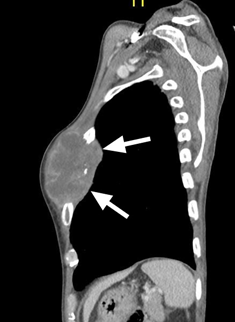

Figure 4 CT scan image sagittal view showing extension of the lesion into the thoracic cavity.

A 59 years old gentleman who was an ex-chronic smoker (40 pack-years) was referred to our centre for a huge left breast mass. On further history, the patient claimed that the left breast swelling has been there for the past one year and he never seek any medical treatment. While in the ward patient developed generalized tonic-clonic seizure (GTC) for six episodes, aborted by intravenous Phenytoin. An urgent brain computed tomography (CT) was performed and a left frontal intra-axial space-occupying lesion was found. Clinically, the left breast swelling was irregular in shape, measuring about (18x5) cm, hard, non-tender and fixed to the underlying structures. There were left axillary lymph nodes palpable. A TRU-CUT biopsy of the left breast mass was performed and histopathology results came out as Invasive breast carcinoma of no special type (NST).Contrasted tomography (CECT) of the thorax was performed for the staging purpose and was reported as the presence of lobulated heterogeneously enhanced mass occupying the whole left breast measuring (11.1x4.7x9.2) cm with an erosion of the left anterior end of second to fourth lateral surfaces of the ribs. Also, there were multiple enhancing axillary lymph nodes bilaterally, at the pre-tracheal, para-tracheal, sub-carina and the presence of lung nodule in the superior segment. There was metastatic lesion seen on the left adrenal gland measuring (3.7x2.9x3.5) cm as well. The patient was staged as T4N1M1. No surgery was done as patient deteriorated and succumbed to death due to Pulmonary Embolism (PE) on day eleventh of admission (Figure 3–5).